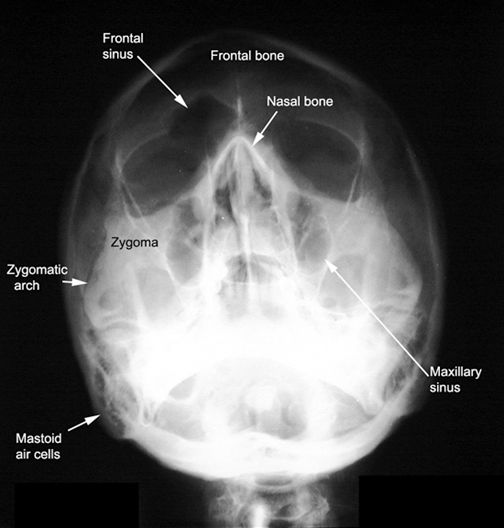

Identify the structures. Click the image for labeling.